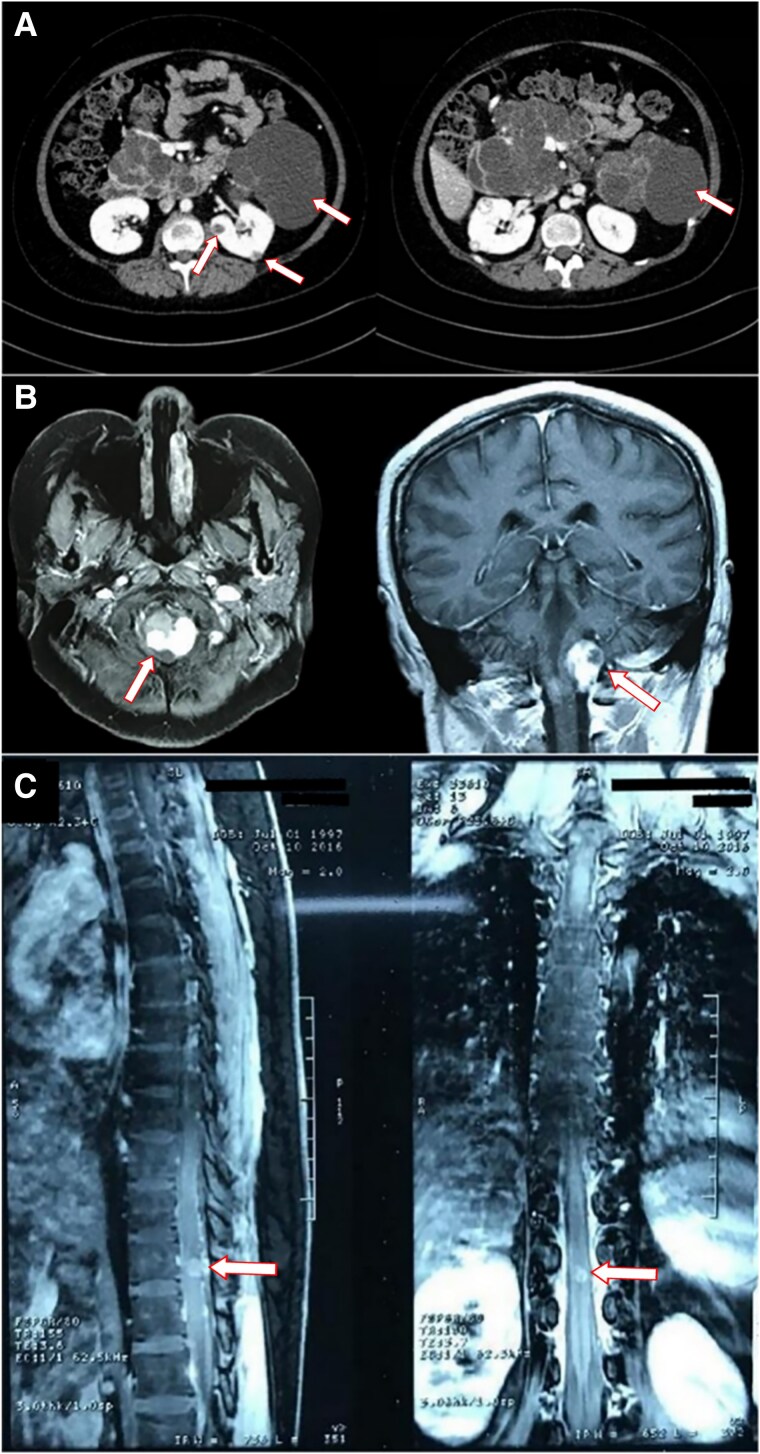

Von Hippel-Lindau (VHL) disease is an autosomal dominant disorder caused by germline pathogenic variants of the VHL gene, which can lead to abnormal growth of blood vessels and cause the development of benign or malignant tumors, as well as cysts in diverse organs. To date, no case reports have documented adrenocorticotropic hormone (ACTH)-secreting adenomas in individuals with VHL disease. We present the case of a 19-year-old female individual with VHL disease who developed an ACTH-secreting adenoma alongside hemangioblastomas in the central nervous system (CNS) and cystic lesions in diverse organ systems. Genetic testing and immunohistochemistry of the pituitary tumor were performed. Genetic testing revealed that the patient carried the familial germline pathogenic variant located in the first exon of the VHL gene (c.227_229del, p.76delF). Immunohistochemical staining of the pituitary tumor demonstrated positive for ACTH, chromogranin A, and synaptophysin, with Ki-67 index at 3%. In addition, tumor cells showed scattered immunoreactivity for the α subunit of hypoxia-inducible factor (HIF-1α). This case suggests that VHL disease might be associated with ACTH-secreting adenomas and broadens the tumor spectrum.

Abstract Image